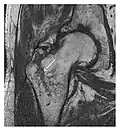

The greater tuberosity of the humerus is also an illustrative location of occult fractures. The osseous injury may follow seizures, glenohumeral dislocation, forced abduction, or direct impaction. They are commonly discovered on MRI in symptomatic patients with suspicion of rotator cuff tear. Coronal images are best suited for detection. They appear as crescentic oblique lines surrounded by a bone marrow edema pattern (Figure 5). The rotator cuff must be inspected since associated ligamentous lesions are common. In the ankle, malleoli and tarsal bones should be checked carefully for any cortical disruptions and radiolucent lines that may reveal a fracture. Awareness of the exact location of the pain will help direct the attention of the interpreter when searching for very subtle signs of fracture (Figure 6).[1]

-

a -

b

Figure 6: Subtle anterior talar fracture in a 39-year-old man presenting with ankle pain after a fall. (a) Anteroposterior radiograph shows a subtle oblique radiolucent line through the talus (white arrows). (b) Sagittal CT reformation confirms the presence of an anterior talar fracture with cortical offset (black arrow). Avulsion fractures, which consist of a detached bone fragment resulting from a ligament or tendon pulling away from the bone, may also present with subtle radiographic signs. Tiny osseous fragments near the presumed attachment site of a ligament suggest this diagnosis. Common sites are the lateral tibial plateau (the Segond fracture), the spinal tuberosity of the tibia resulting from anterior cruciate ligament avulsion, and the ischial tuberosity.[1]